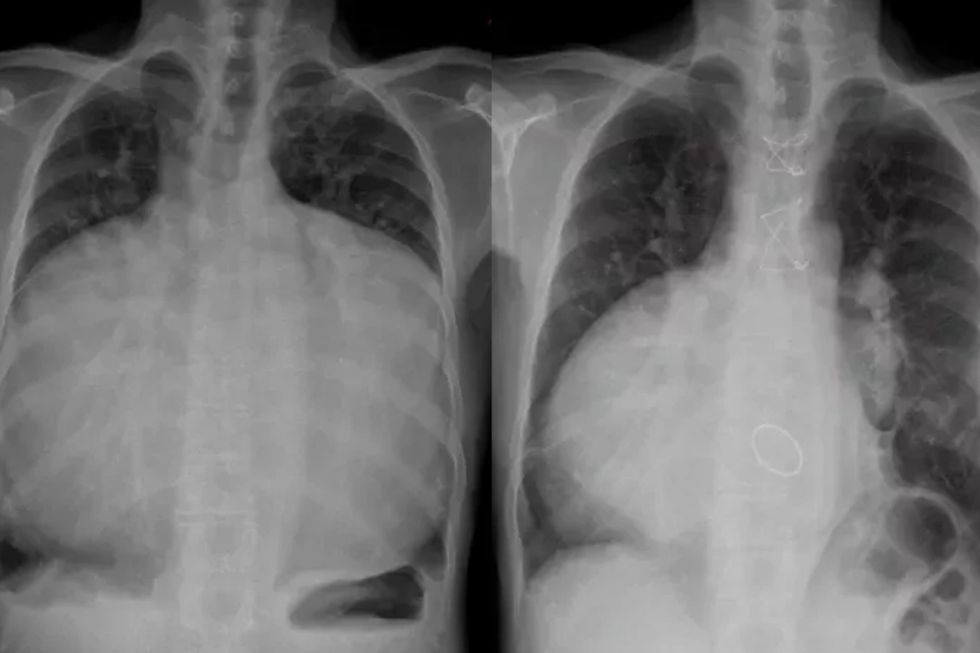

When doctors performed a chest X-ray, they found “gross cardiomegaly” – essentially an enlarged heart.

A cardiothoracic ratio (CTR), which measures the ratio of the heart and to what extent it fills the chest cavity, was measured. A CTR of 1 revealed that the man’s thoracic cavity was entirely filled by his heart.